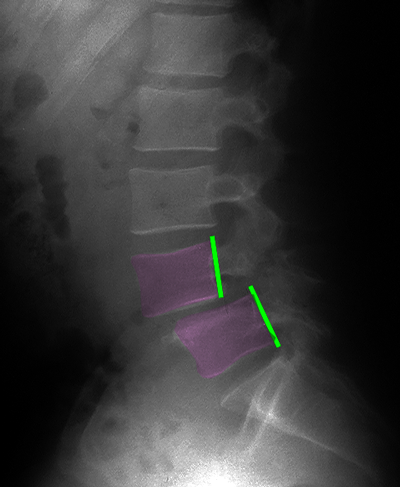

Σπονδυλολίσθηση 3ου βαθμού Ο5-Ι1, ισθμική. Η προσθιολίσθηση του Ο5 σπονδύλου επί του Ι1 απεικονίζεται με την απόσταση ανάμεσα στα οπίσθια τμήματα του σώματος των σπονδύλων (πράσινες γραμμές). Το νευρικό τρήμα παρουσιάζει σημαντική στένωση στο επίπεδο της σπονδυλολίσθησης (κίτρινος κύκλος, τρήμα με φούξια, νεύρο με μπλέ) σε σχέση με το άνωθεν αυτού φυσιολογικό (κυανό βέλος). |